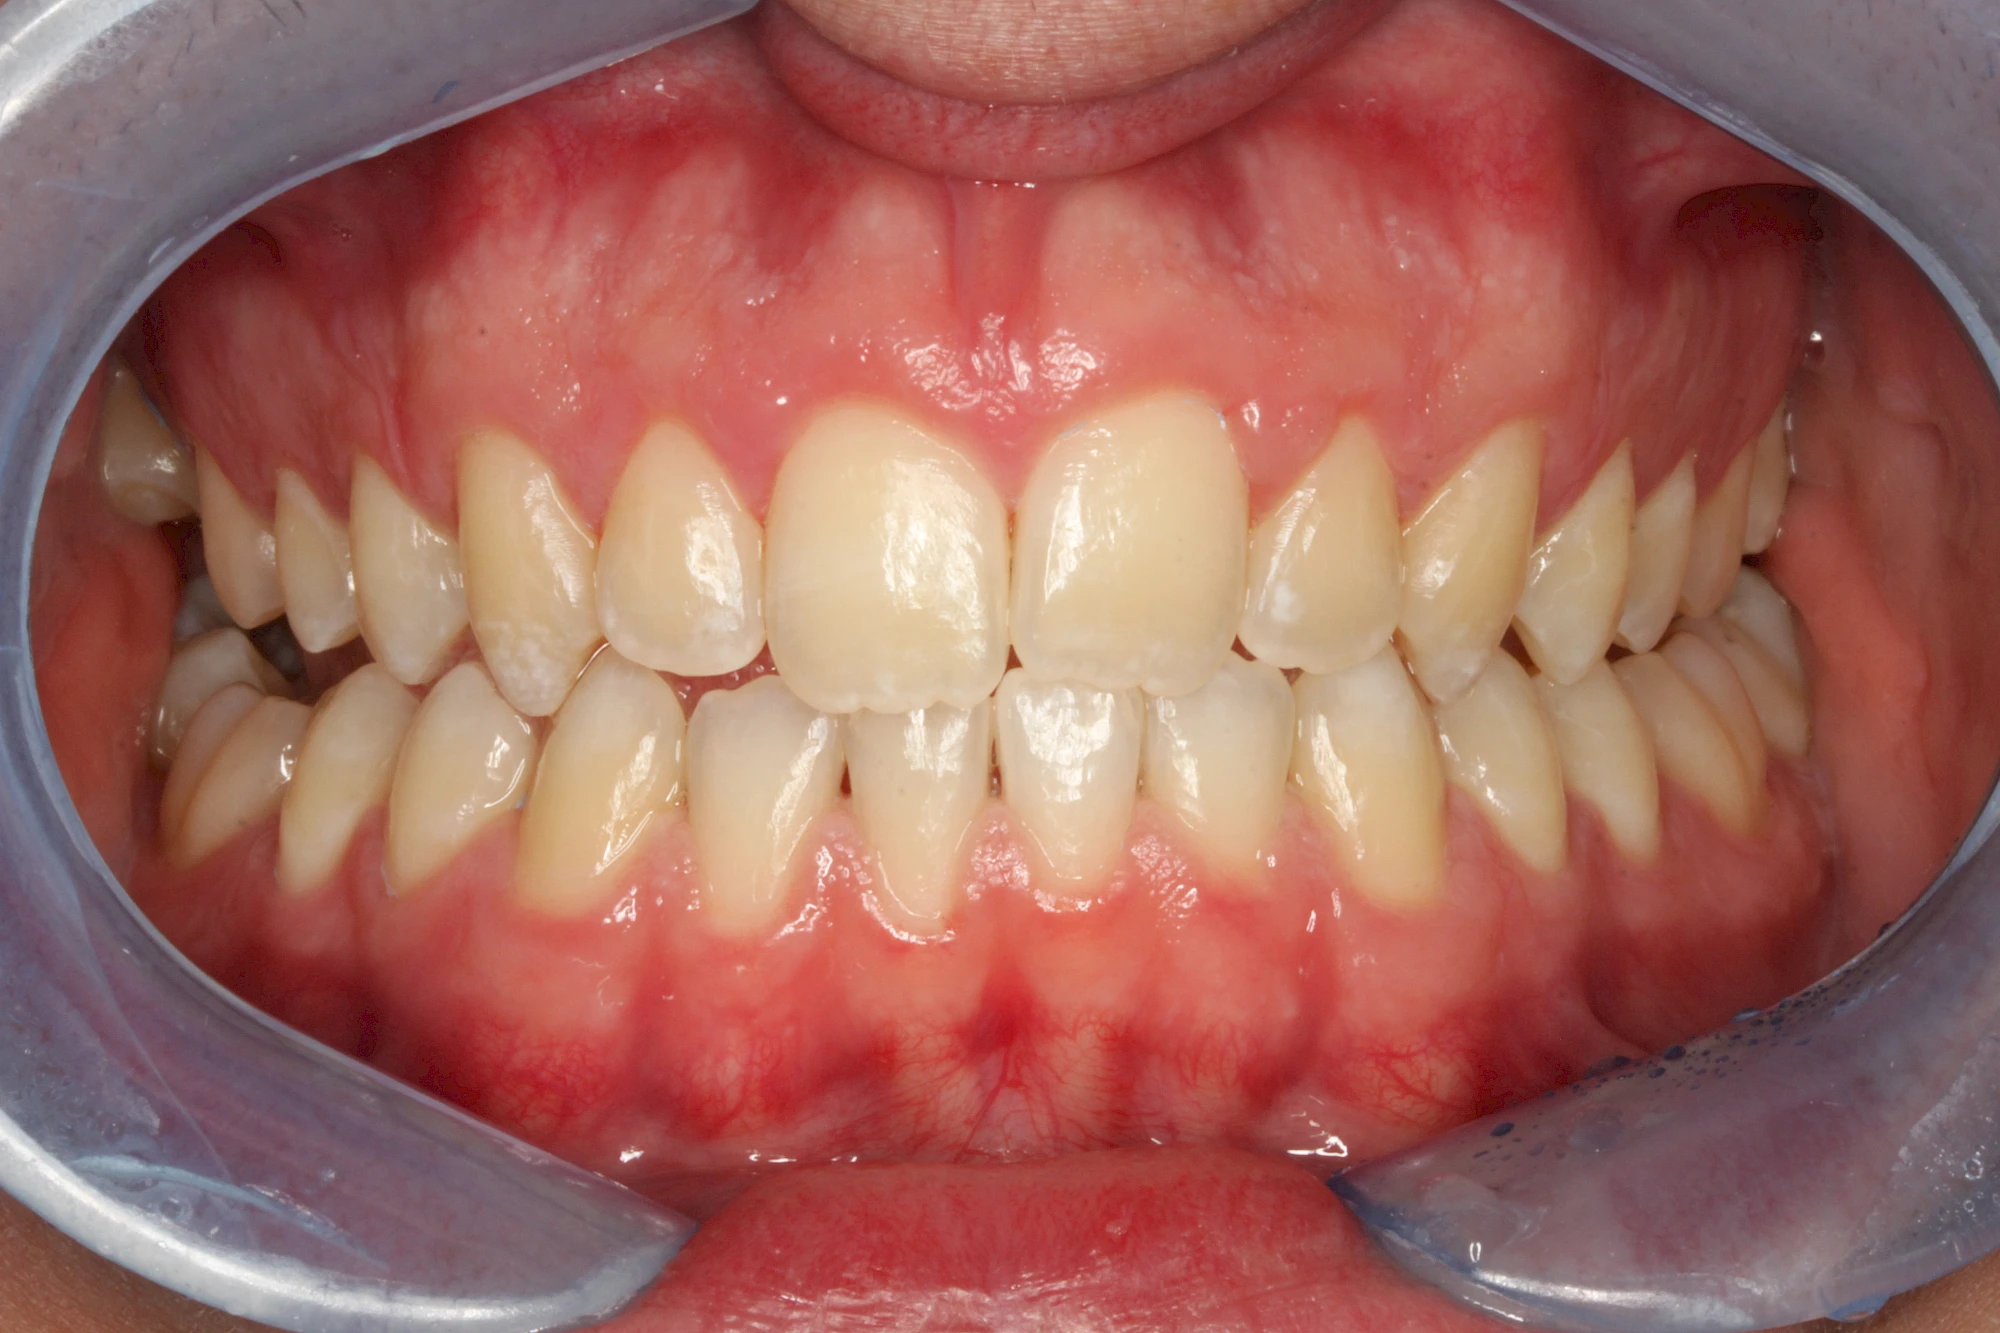

Verfärbungen an Zähnen können außen aufgelagert oder im Zahn eingelagert sein.

Von innen (endogen)

- Durch übermäßige Fluorideinlagerung in der Zahnreifung (mehrere Zähne, weißlich-fleckig)